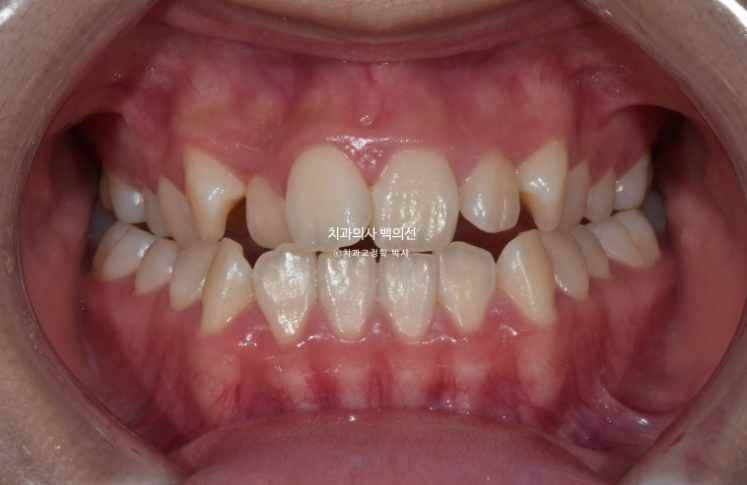

23년 10월에 교정치료를 위해 내원한 중학생 아이입니다.

23.10

앞니에 개방교합이 보이고 앞니뿐 아니라 어금니까지 반대교합이 보입니다.

옆모습 엑스레이 분석 결과 경미한 주걱턱으로 진단이 되었고 성장이 거의 완료가 되어 바로

교정치료에 들어갔습니다.